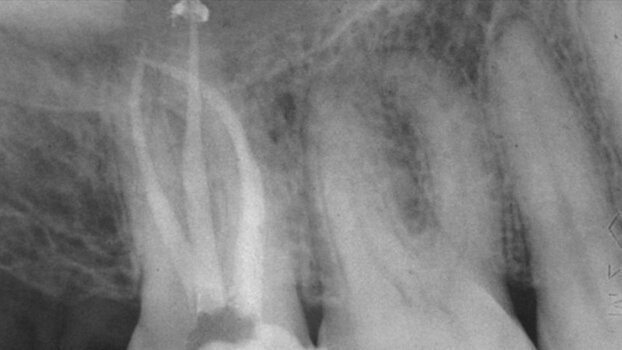

A medically and periodontally stable 37-year-old man presented with coronally fractured tooth #9, which had a history of endodontic treatment (Figs. 1a ...